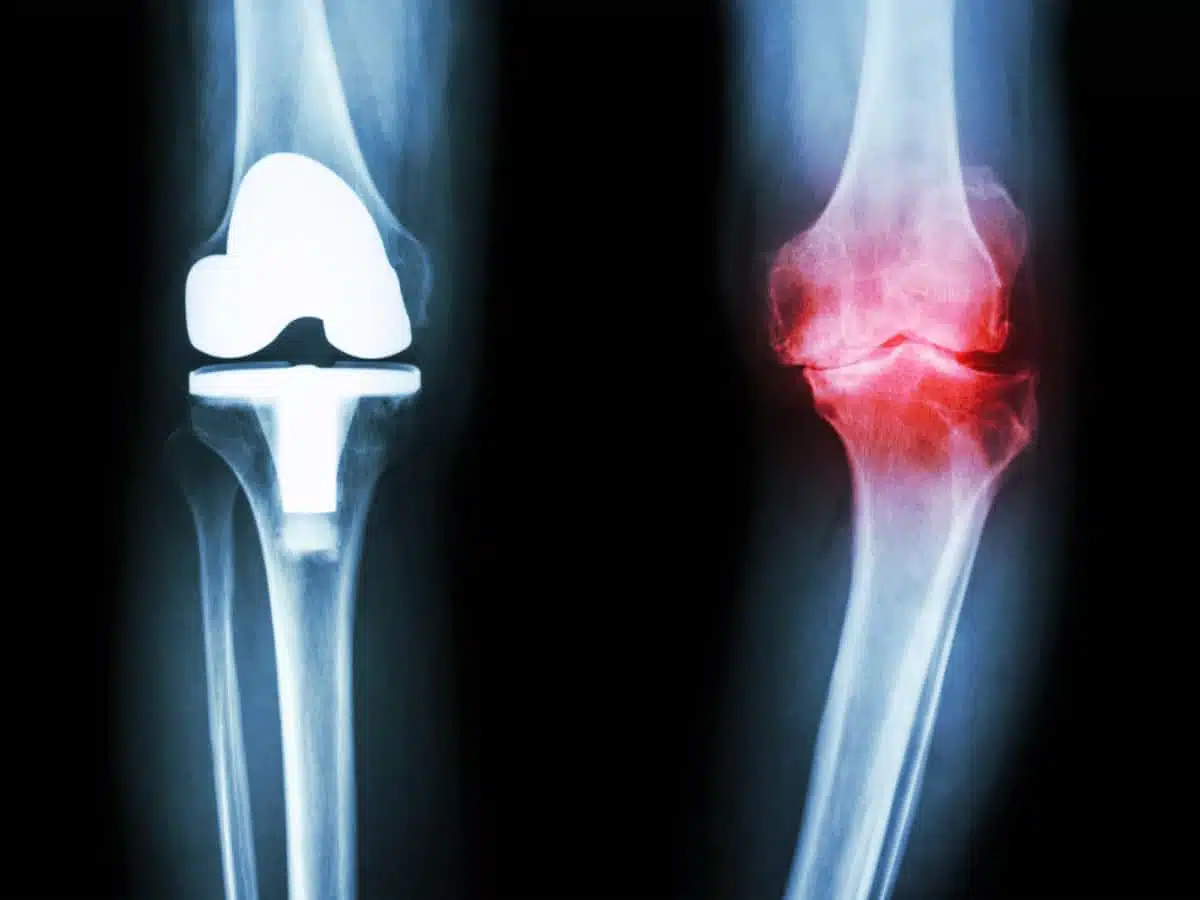

هناك العديد من الحالات التي تعاني من آلام خشونة الركبة، وهي حالة شائعة تؤثر بشكل كبير على حياة الأشخاص، حيث تصيب مفصل الركبة وتحدث نتيجة تآكل وتكسير الغضروف، ومن خلال المقال التالي سنتعرف على درجات الخشونة والاختلافات فيما بينهم.

من المعروف أن خشونة الركبة من الأمراض التي لابد من معالجتها بمجرد ظهور الأعراض ويتم التشخيص لتجنب تعرض المريض للمضاعفات وتختلف طريقة العلاج المستخدمة حسب درجة الخشونة الحادثة، ومن درجات خشونة الركبة:

• الدرجة الأولى: عادة لا يشعر المريض بألم في هذه المرحلة حيث تكون طفيفة ولا تؤثر بشكل كبير في المفصل، ويحدث تآكل بسيط للغضروف ونتوء عظمي طفيف.

• الدرجة الثانية: تكون درجة الخشونة خفيفة ولا يظهر بشكل طبيعي يكشف عنه في الأشعة السينية وتكون النتوءات العظمية أكثر وضوح ولكن العظام والغضاريف تكون سليمة ويشعر المصاب به بألم بسيط بعد ممارسة أنشطة رياضية أو الحركة.

• الدرجة الثالثة: تكون الخشونة في هذه المرحلة تسبب تآكل في الغضروف بشكل ملحوظ مما يتسبب في تضيق المسافة ما بين العظام، ويشعر في هذه المرحلة المصاب بألم متكرر في الركبة عند المشي أو عند تحريك المفصل، كما يحدث تصلب بعد الجلوس مدة طويلة أو عند الاستيقاظ من النوم.

• المرحلة الرابعة: المرحلة الأخيرة من خشونة الركبة من أكثر المراحل خطورة لمريض خشونة الركبة، نتيجة حدوث تآكل بشكل متطور وملحوظ للغضاريف، مما يسبب حالة من الفقدان الكامل للغضروف ويرجع ذلك نتيجة نقص السائل الزلالي، وفي هذه الحالة يشعر المريض بألم شديد ويسبب صعوبة في الحركة وتيبس العضلات والمفصل بالكامل عند الحركة وعند الراحة.